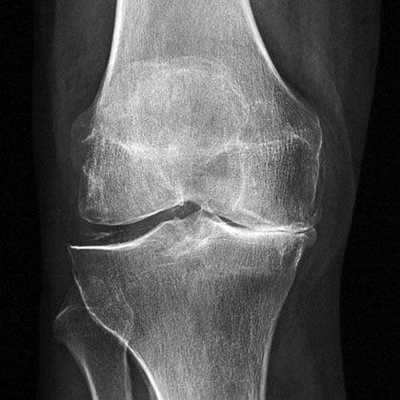

Имплант на рентгене.

Артроз коленного сустава на рентгене.

А так выглядит пораженный сустав через артроскоп. Обратите внимание на площадь отсутствия хрящевой поверхности.

Показания к замене

Посмотрите на рентген, на нем вы видите, до какой степени при запущенном гонартрозе изношен гиалиновый хрящ, обеспечивающий гладкое скольжение суставных поверхностей. Концевые участки костей грубо деформируются нарушая функции сгибания и разгибания конечности вызывая интенсивный болевой синдром.

Сравнение здорового и пораженного сустава.

Динамика болезни на рентгене.